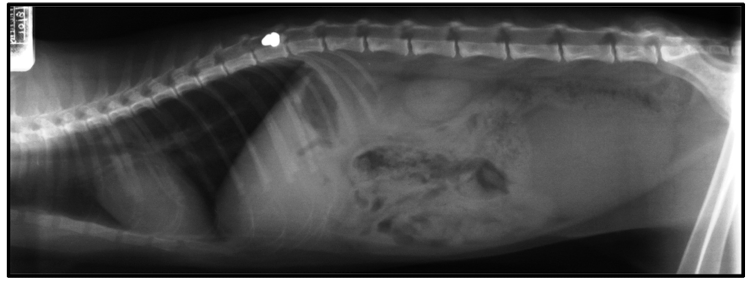

4. Temporarily immobilize in lat. recumbency (secure pt. to rigid platform), w/out interfering w/ respiration, and obtain radiographs

When imaging confirms SC compression (displaced fx fragment; disc rupture; compressive hematoma; penetrating missle)